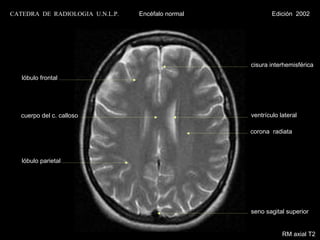

CATEDRA DE RADIOLOGIA U.N.L.P.   Encéfalo normal           Edición 2002

cisura interhemisférica

lóbulo frontal

cuerpo del c. calloso                           ventrículo lateral

corona radiata

lóbulo parietal

seno sagital superior

RM axial T2